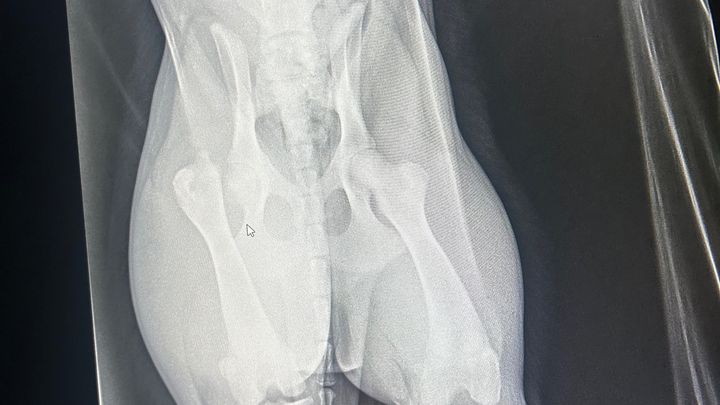

We have 2 puppies that we got back in October, and one of them, Sammie, got out and got into the road and was sadly run over by a truck. It could be a lot worse, but bless her heart, it broke her hip bone, and she's going to need surgery to fix it. She is in so much pain and it breaks my heart to see her hurting and feeling helpless. We have contacted a surgeon in Jonesboro, and they can do the surgery, but it's a lot more than I can do at this time. We appreciate any help. Thank you all so much!